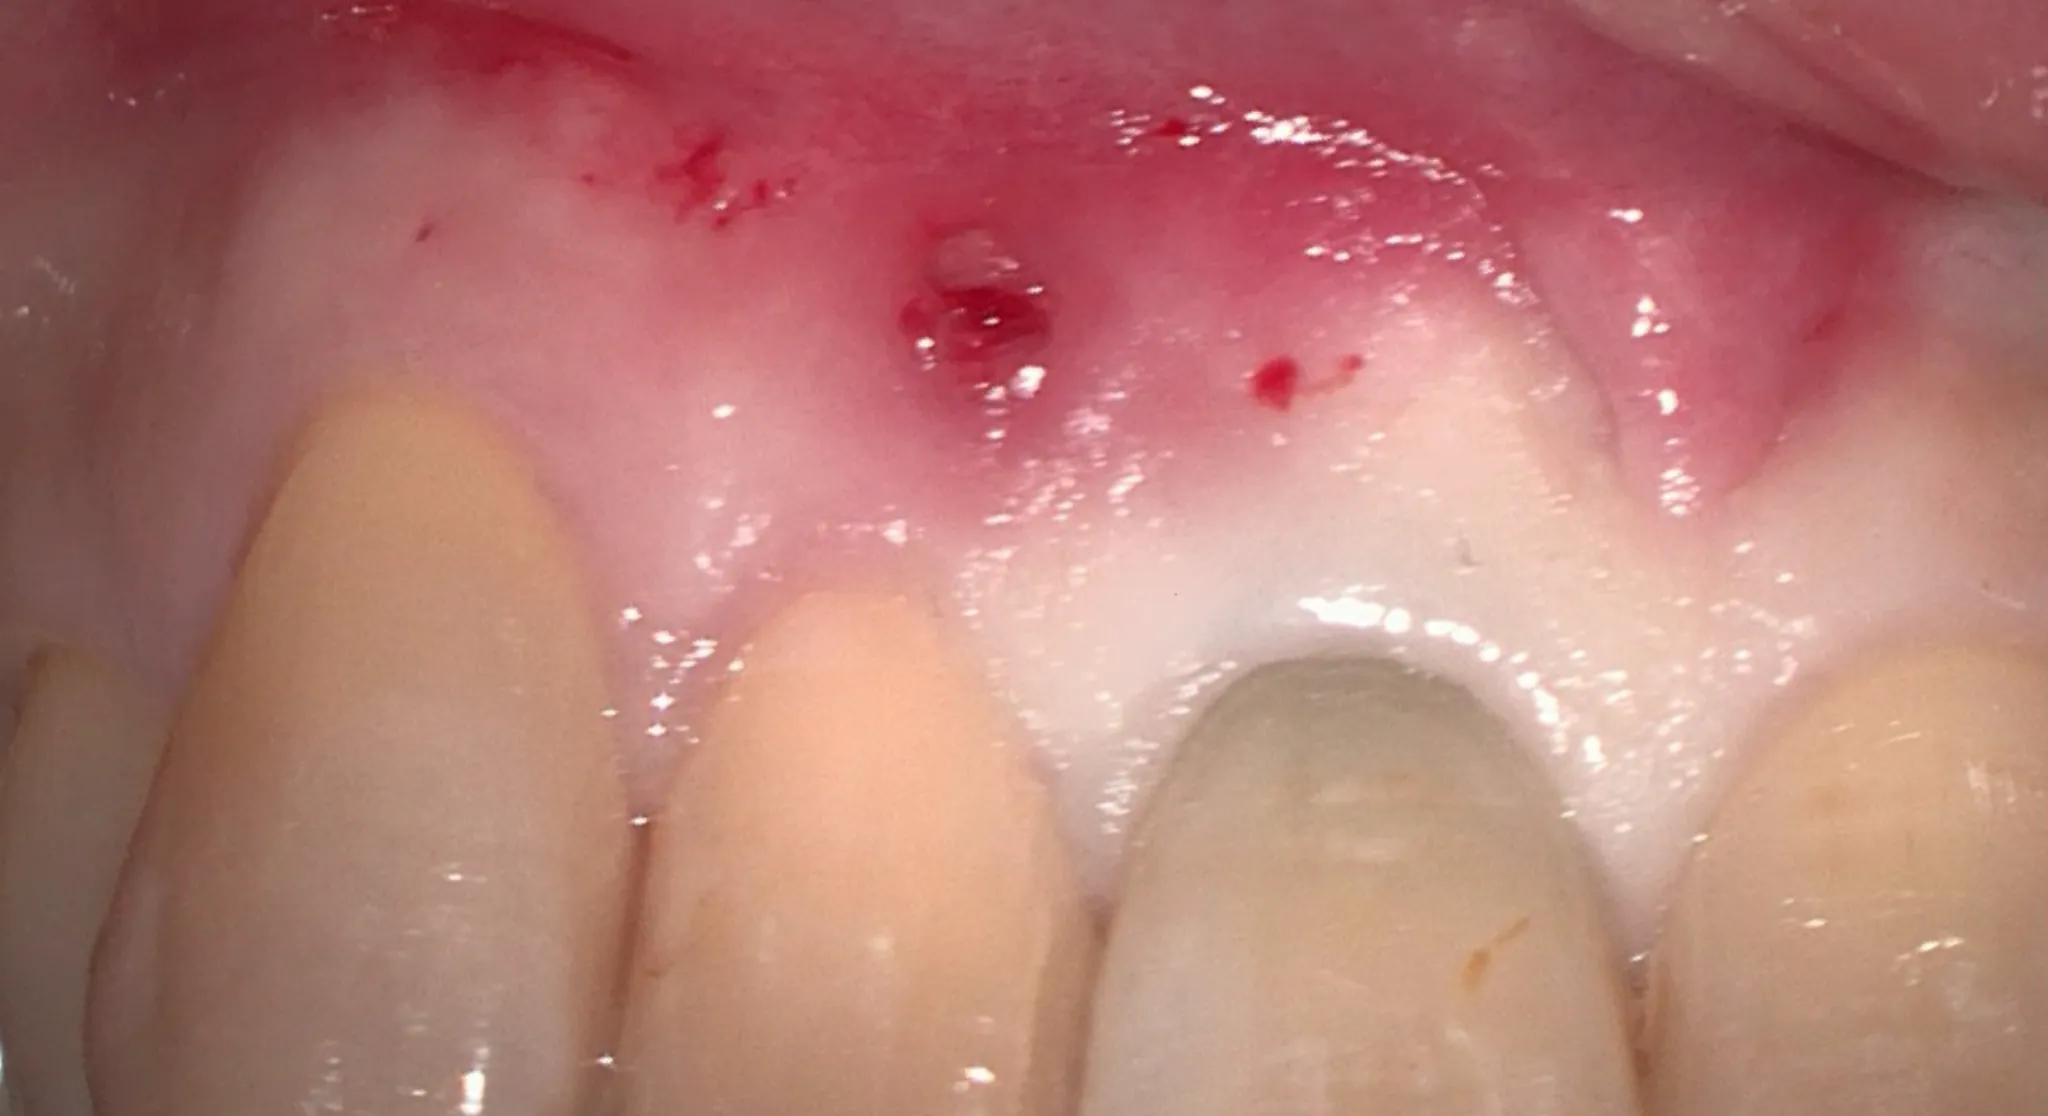

当院では、最新の技術を積極的に導入し、精度の高い治療を提供しています。

特に、すべての治療においてマイクロスコープを導入することで精密な治療を実現します。

最新技術の導入により治療の精度が向上し、再発のリスクを減らすことができるため、患者さんにとっての長期的な健康を守る重要な手段となっています。 -